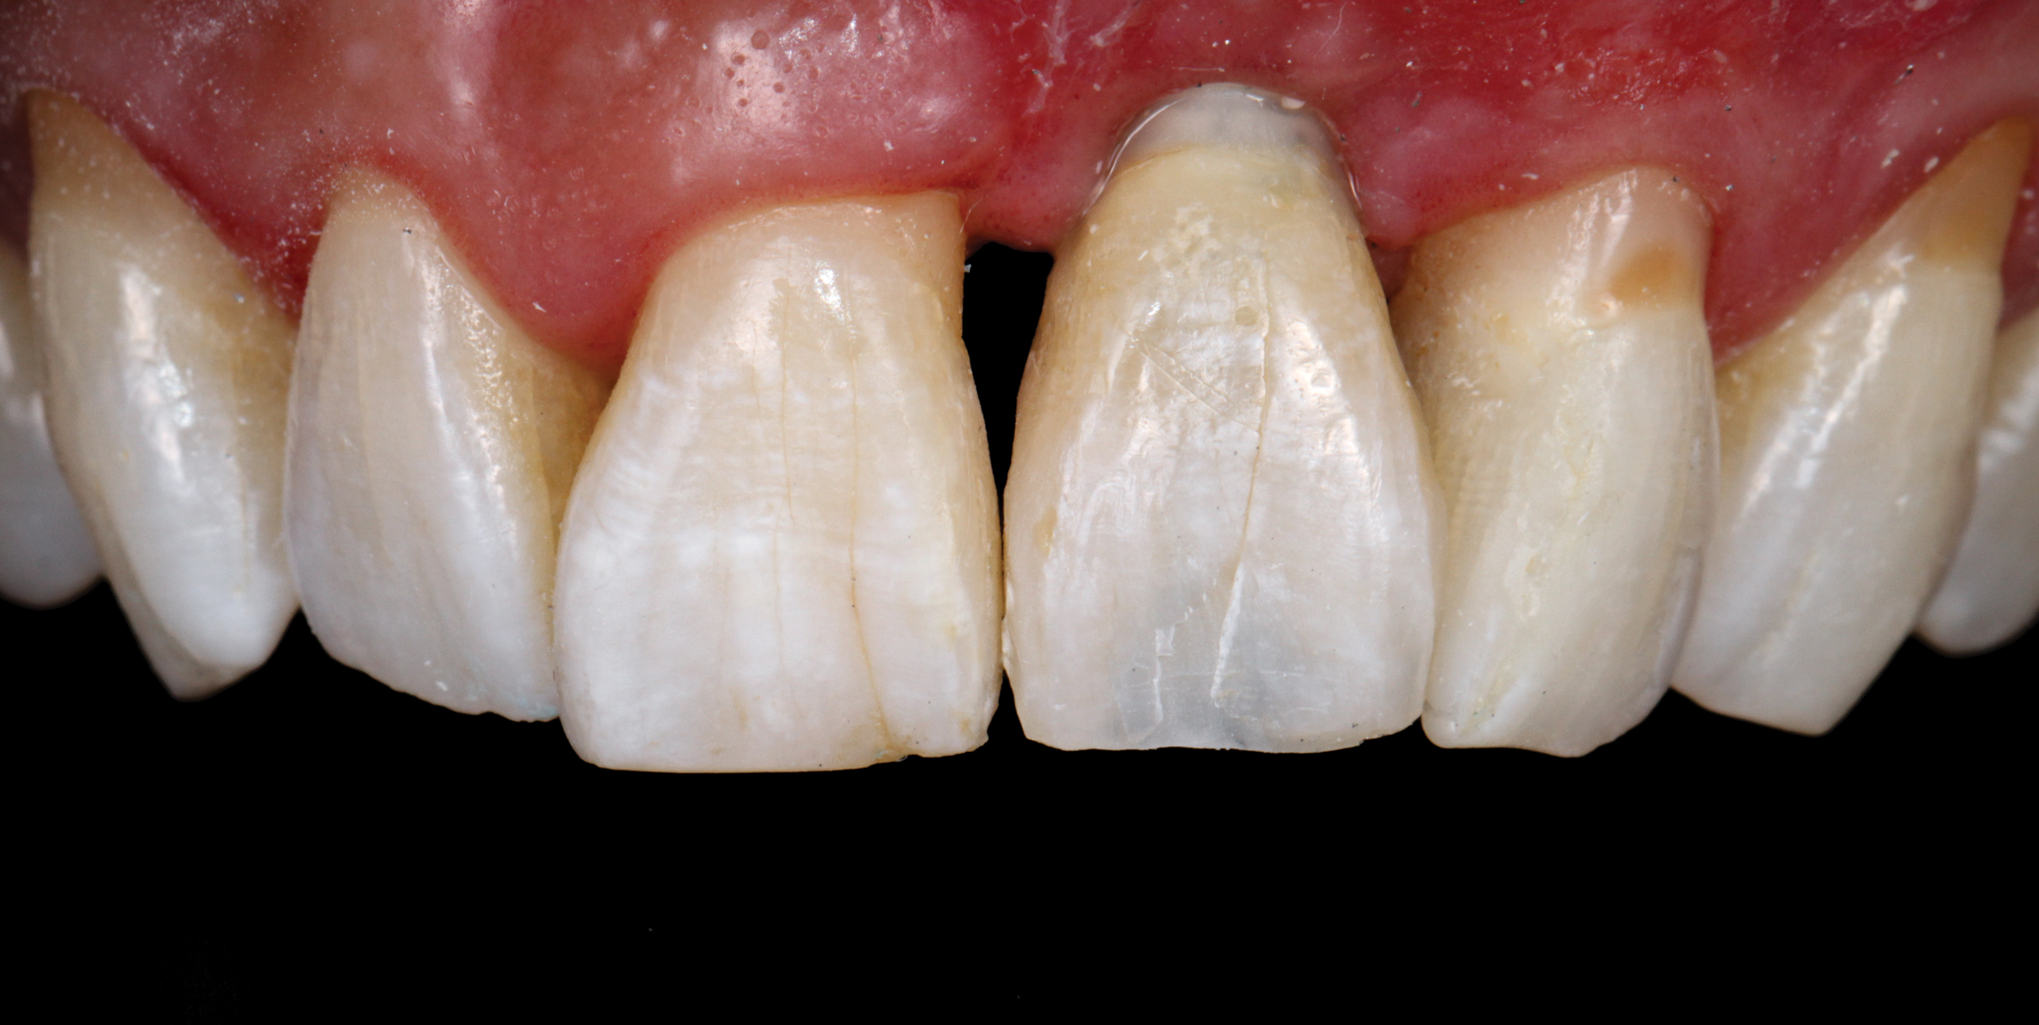

(45.) A patient presented for the replacement of the maxillary left central incisor with a bonded pontic made from the natural tooth, which was removed.

Figure 45